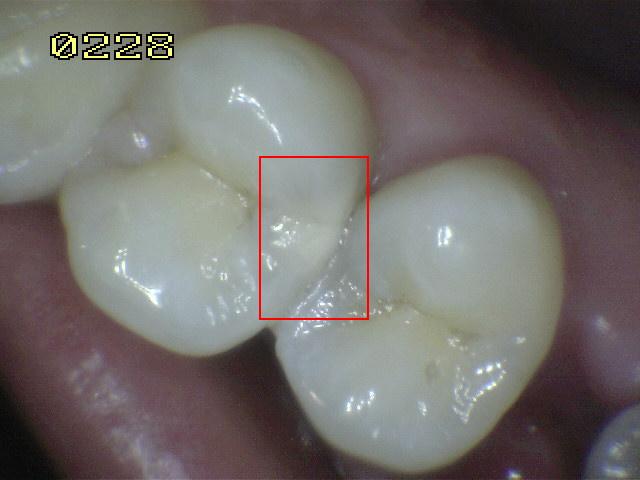

Código 3

(Caries Moderada): Ruptura

localizada del esmalte debido a caries sin dentina visible.

-

La superficie seca muestra una perdida detectable de la

estructura del esmalte. El diente visto en estado

húmedo pueden tener una clara opacidad de caries (mancha blanca

/ marrón)

Una

sonda paeriodontal puede deslizarse sobre la

lesión para comprobar micro-cavidad (pérdida de la

integridad de la superficie de esmalte < 0,5 mm.)